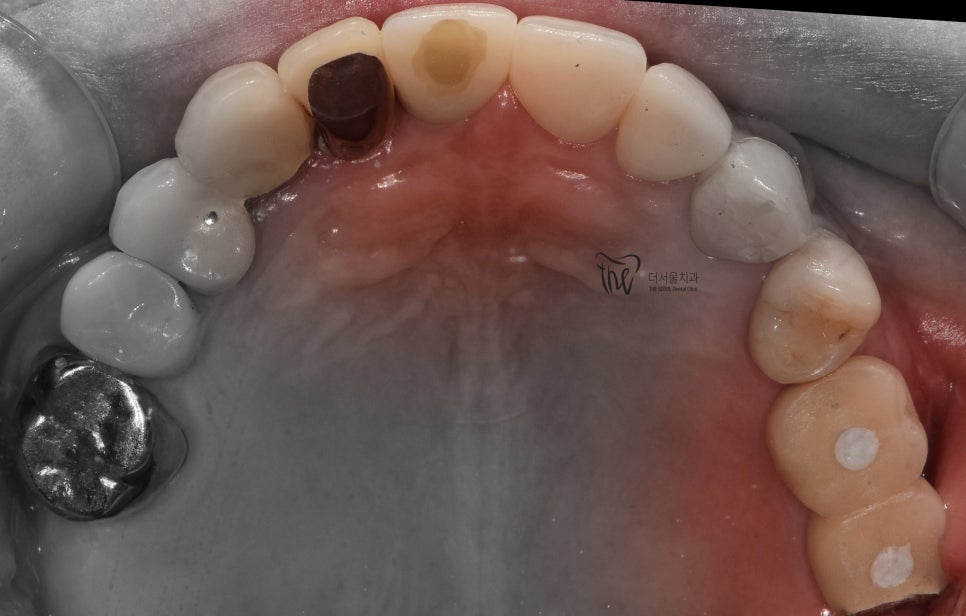

『증례 설명, 80세 환자』

구강 내 여러가지 문제점을 안고

더서울치과에 찾아오셨었습니다.

이미 연세도, 80세가 넘으셨기 때문에

구강 내 노화도 충분히 진행이 된 상태였습니다.

- 보철 하방 2차 우식증 발생

- 앞니 통증 호소 및 미세한 크랙, 우식증 발견

- 구치부 치관 소실 및 잔존 치근만 존재

이런 상황을 안고 오셨으며, 치과에 오실 때 부터

치아 통증을 호소하셨던 분입니다.

구강 내 사진을 보면, 이미 치은 퇴축이 상당히

진행 된 것을 볼 수 있으며 곳곳에 구강 위생 관리가

잘 되어있지 않은 것을 같이 볼 수 있었습니다.